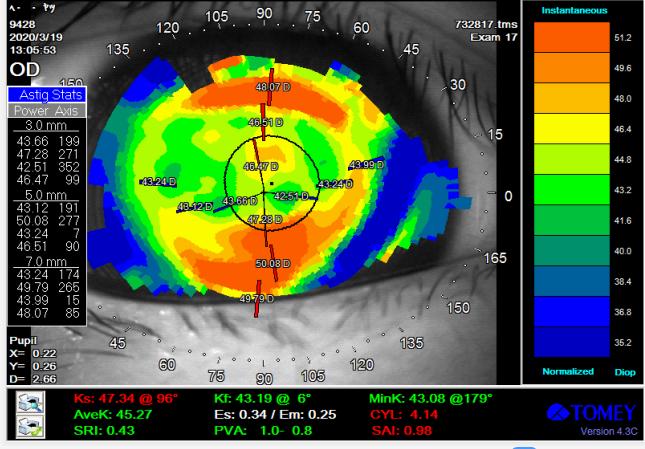

其原始角膜地形图如下:

从地形图发现双眼角膜散光大于300度,但基本是上下对称的角膜形态。